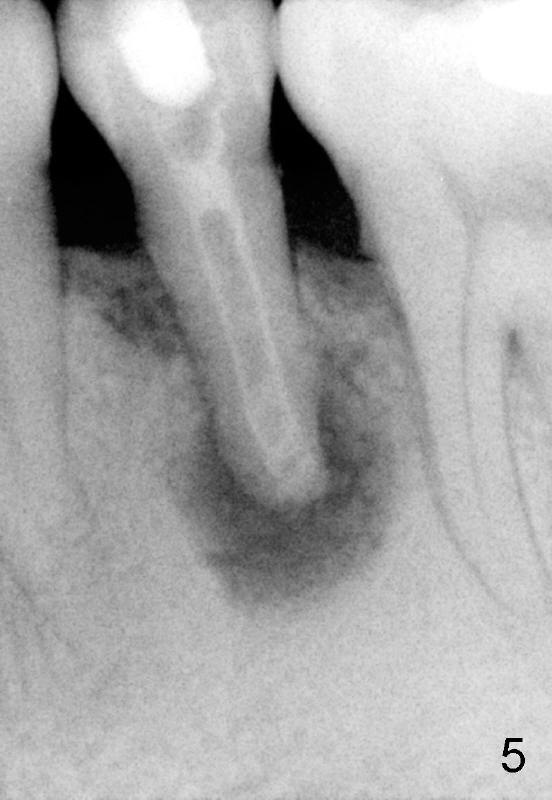

A 40-year-old Chinese man has periodic (once a month) mild pain and swelling in the lower left quadrant. Clinical exam reveals dens evaginatus (Fgi.1': <) in #20. Upon pressure from mouth mirror handle, there is limited amount of purulent discharge from the fistula (Fig.1": <). Preop PA shows a large canal with large periapical radiolucency (Fig.1). RCT started on Aug 6, 2010 with #70 file at 20 mm (Fig.2), #120 file at 16 mm (Fig.3) and CaOH paste in the canal (Fig.4). The dressing changed on Oct 8, 2010 (Fig.5). RCT finished on Jan 25, 2011 with master cone (rolled with several gutta perchae) (Fig.6), lateral condensation (Fig.7) and after vertical condensation and build-up (Fig.8). The canal was wet in the last two appointments with no sign of apexification. Follow up is done in 7 months (Fig.9), 11 months (Fig.10) and 18 months. Although the patient reports no pain after the treatment, the fistula remains with purulent discharge. The patient does not accept apical surgery. What should we do? Retreat with MTA (1,2,3)?